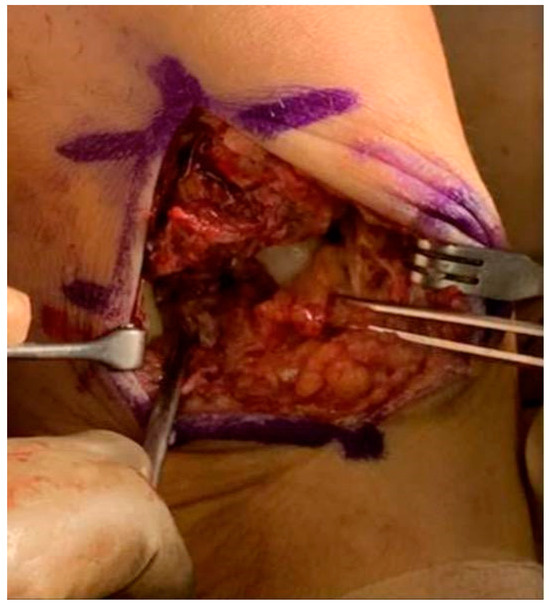

Background/Objectives: Endoscopic biliary stenting is the standard palliative intervention for malignant biliary obstruction, aimed at restoring ductal patency. Radiofrequency ablation (RFA) has been introduced as an adjunct technique to improve stent durability and patient outcomes. However, the literature remains inconclusive regarding which patients are most likely to benefit from the combination of RFA and stenting. Methods: We retrospectively described clinical outcomes of 24 patients undergoing endobiliary RFA combined with biliary stenting for malignant biliary obstruction. Post-procedural and 6-month outcomes were assessed using technical success and changes in serum bilirubin; procedure-related adverse events were extracted from available medical records. Results: Nineteen females and five males were included in the study. The most prevalent diagnoses were metastatic adenocarcinoma (n = 8) and cholangiocarcinoma (n = 6). 25% of patients did not complete the 6-month follow-up due to malignancy progression. 16 out of 18 maintained the patency of biliary stents. Repeat endoscopic intervention for suspected stent dysfunction was documented in one patient. When analyzed in an intention-to-treat manner (counting deaths before 6 months as failures), the corresponding 6-month patency/clinical success rate was 16/24 (66.7%). Conclusions: In this retrospective single-center experience, RFA combined with biliary stenting was feasible and was associated with maintained biliary drainage in a majority of patients who survived to the 6-month assessment.